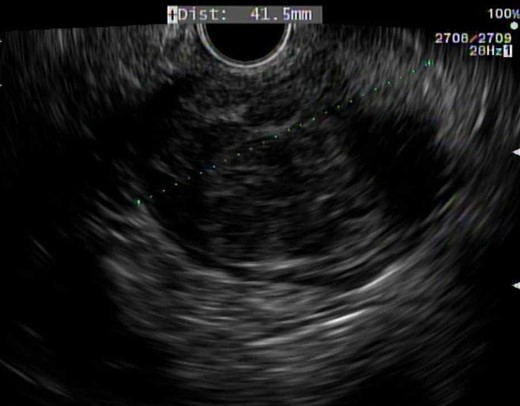

The patient is a 53-year-old male with past medical history significant for type II diabetes mellitus and hypercholesterolemia who underwent routine screening colonoscopy, during which a lobular mass of the proximal rectum was discovered (Fig. 1). The patient subsequently underwent an endoscopic ultrasound (EUS) with fine needle aspiration (FNA) biopsy (Fig. 2). Pathology displayed scant spindle cells with benign glandular epithelium suspicious for a spindle cell neoplasm. Accordingly, the patient was evaluated by a colorectal surgeon for further plan of care. A firm palpable lesion was appreciated on digital rectal exam. Various surgical approaches including laparoscopic low anterior resection as well as transanal excision were discussed with emphasis on complete excision due to the possibility of malignancy. The patient was taken to the operating room and an approximately 3 to 4 cm mass of the mid-rectum was appreciated; as the mass was found to be mobile, it was excised transanally by means of a stapler. Intra-operative pathological evaluation deemed the mass likely to be a low-grade spindle neoplasm, raising the possibility of a schwannoma or gastrointestinal stromal tumor (GIST). The procedure was well tolerated and the patient experienced full continence postoperatively.